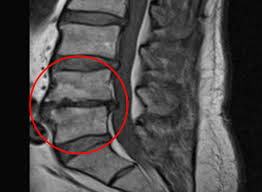

허리협착증을 진단하기 위해서는 전문 의료진의 평가가 필요합니다. 일반적으로 X-ray, MRI와 같은 영상검사를 통해 척추의 상태를 확인하게 됩니다. 이러한 검사는 척추관의 협착 정도를 평가하고, 다른 척추 질환과의 차별화를 가능하게 합니다. 또한, 환자의 증상에 대한 자세한 청취와 신경학적 검사를 통해 진단이 이루어집니다. 따라서 의사와의 상담을 통해 알맞은 진단을 받는 것이 중요합니다.

- X-ray 검사

- MRI 검사